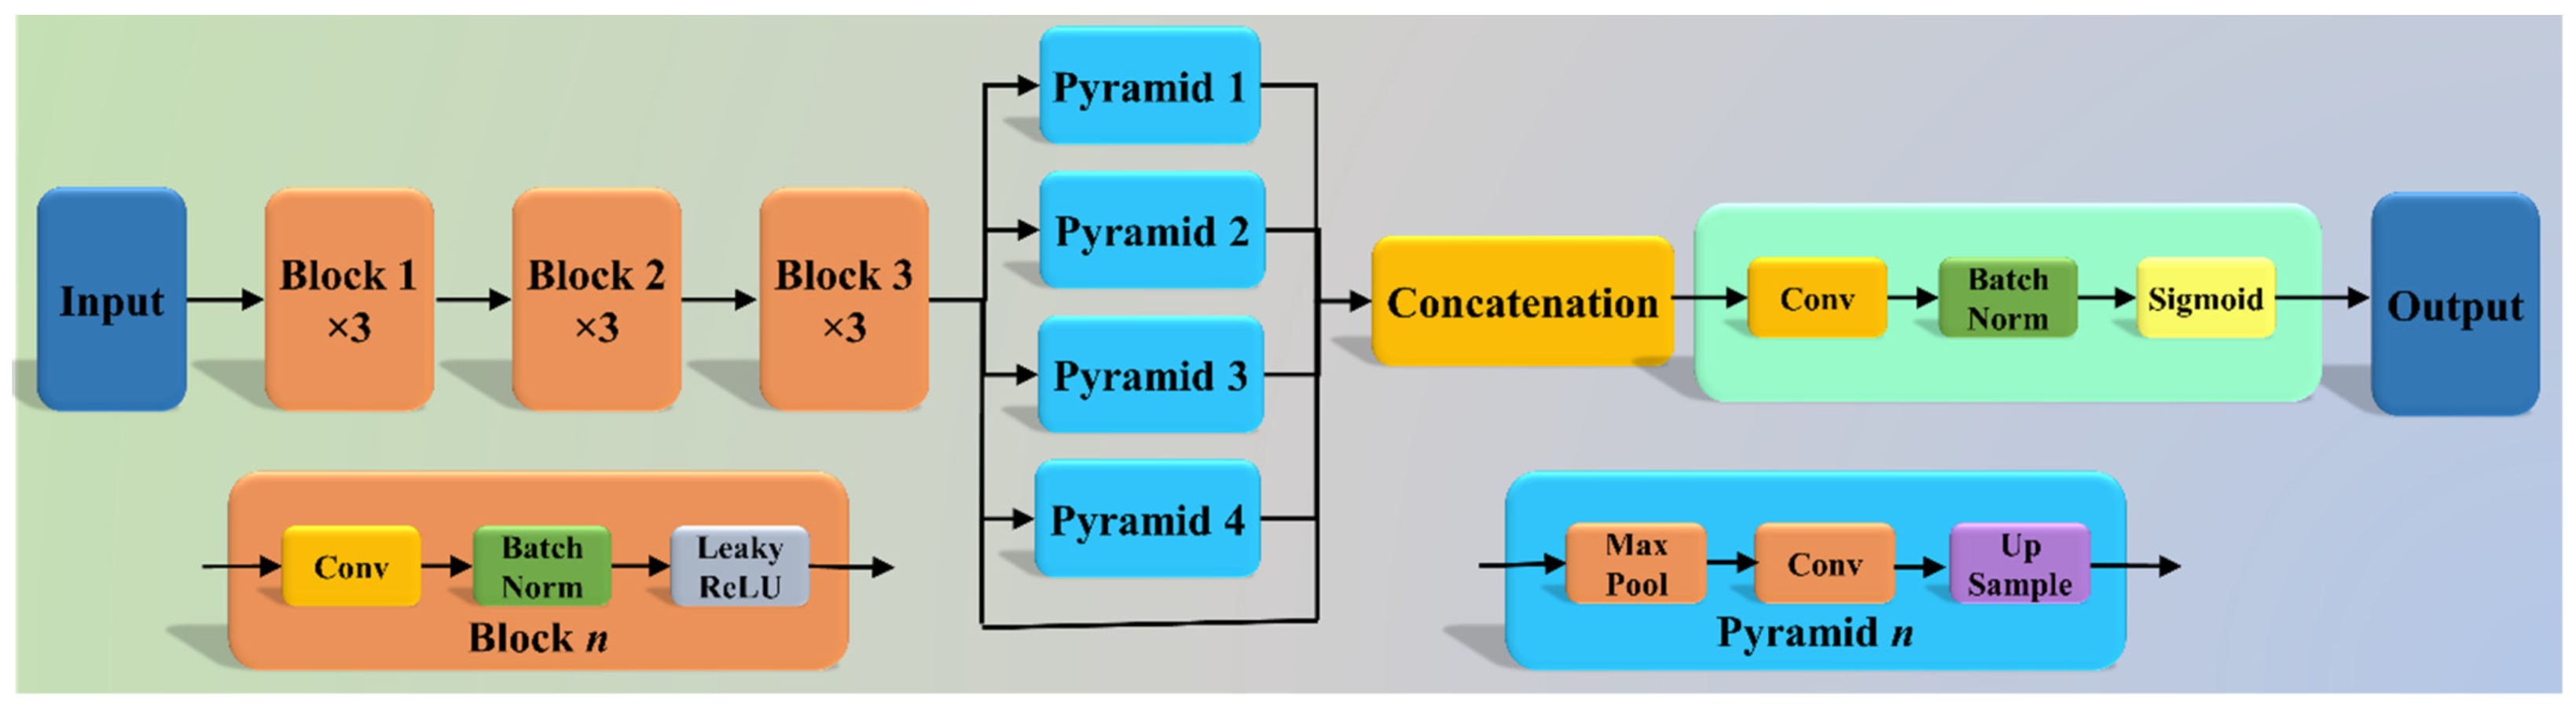

2.2. Architecture

2.2.1. Three AI Models: PSP Net, VGG-SegNet, and ResNet-SegNet

2.2.2. Loss Functions for AI Models